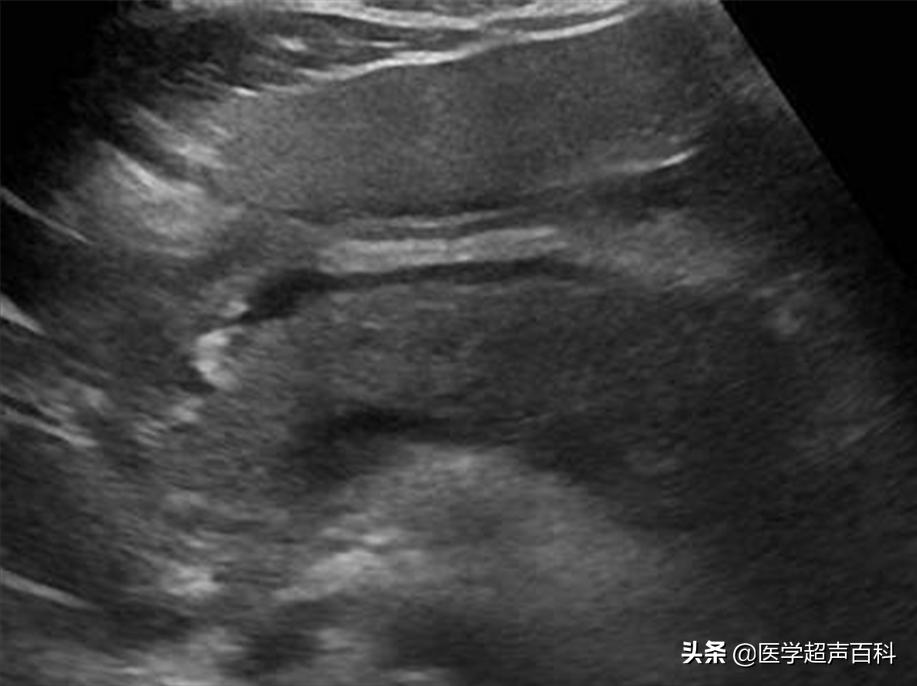

3、接受檢查:一旦被診斷為胰腺炎,患者需接受一系列檢查,如血液檢查、影像學(xué)檢查等,以了解病情嚴(yán)重程度和制定治療方案。